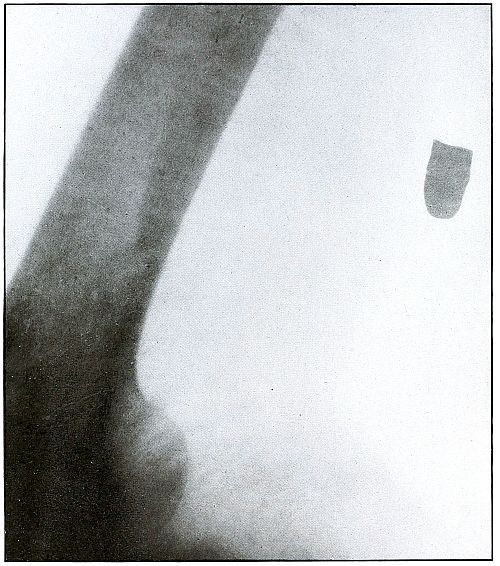

Gunshot fracture, tibia and fibula |

130 |

| 61. |

Gunshot fracture, tibia and fibula |